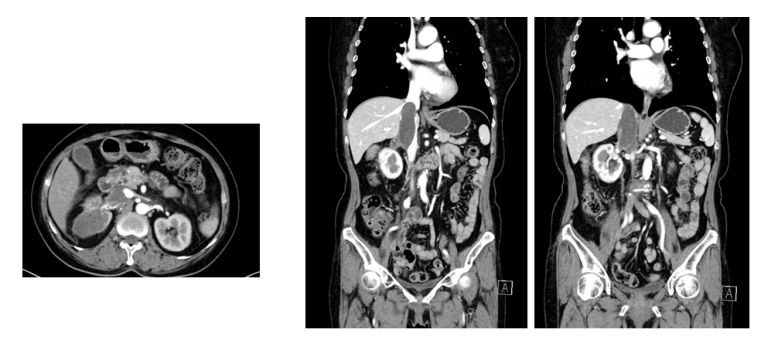

2024年8月2日,继续培唑帕尼800mg po qd;胃肠道反应较重,恶心纳差(AE2-3级)。2024年9月13日、2024年11月1日间断复查胸部+全腹部(含盆腔)CT平扫+增强:右肾中上份见一类椭圆形略低密度灶,较大截面约5.5×4.0cm,边界欠清,增强扫描呈欠均匀轻度强化,较前增大,病灶侵及部分右肾静脉-下腔静脉,以上水平下腔静脉全程粗大,较宽处约3.8cm。两次对比变化不明显。疗效评价:SD

图 2024年9月13日CT复查

图 2024年11月1日CT复查